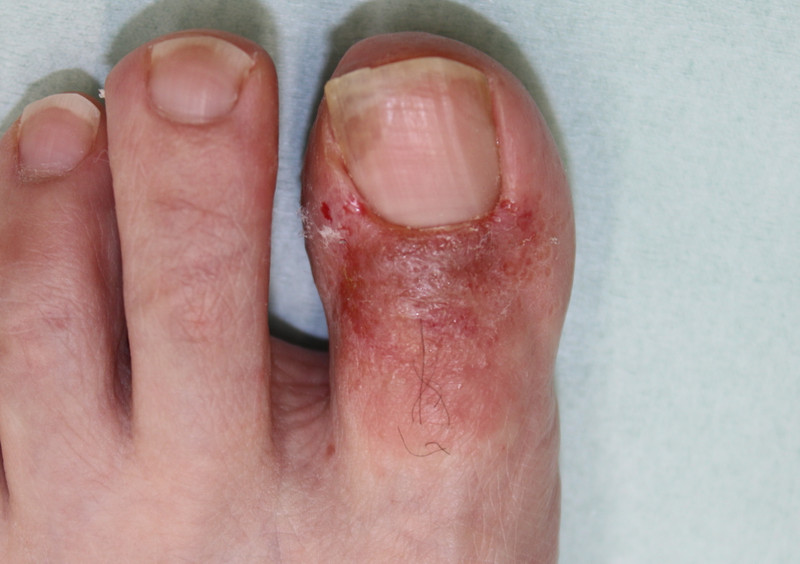

まず一番多いのが、市販薬によるかぶれです。下写真の患者さんは、一生懸命市販の水虫薬をぬっているのですが改善せず悪化してきました![]()

患者さんの心理として、改善しない場合は塗る量が足りていないと勘違いします。さらにたっぷりと何回も外用することでますます悪化していきます

顕微鏡検査で水虫菌(白癬菌)がいないことを確認し、かぶれの治療を開始することが大切です。